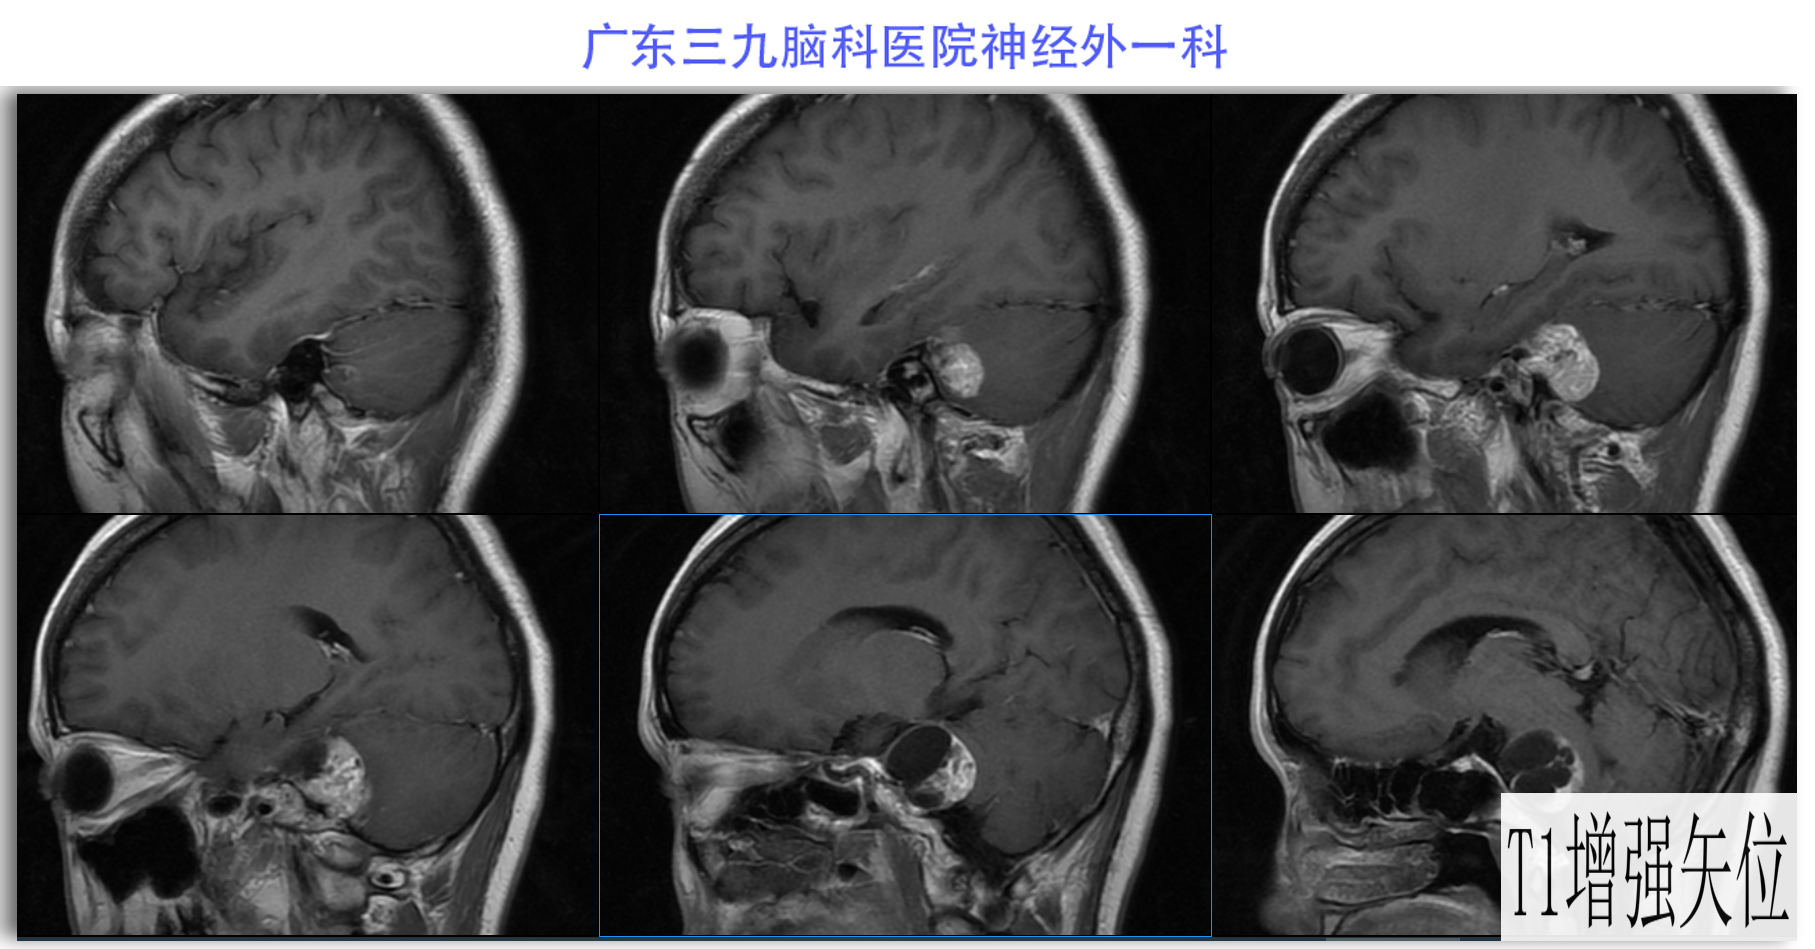

陈某某,女,41岁,因“左侧面部麻木3月余,吞咽困难半月余”于2024-02-17入院。患者3个月前出现左侧面部麻木,偶尔伴有头晕和左侧流泪,但没有听力下降或耳鸣。同时,患者也出现肢体乏力和行走不稳,但未接受任何治疗。半个月前,患者发现吞咽硬质食物稍有困难,同时左侧面部麻木加重。因此,前往当地医院就诊,并进行头颅MR检查,结果显示左侧CPA区存在占位性病变。为了进一步治疗,患者转诊至我院就医。术前检查显示:左侧角膜反射减弱,左侧鼻唇沟略微变浅,伸舌稍微右偏,咽反射迟钝。门诊诊断为“左侧巨大听神经瘤”,收治至我科进行住院治疗。手术过程顺利,术后患者恢复良好,面部轻度瘫痪与术前相同。术后病理检查结果确认为听神经瘤。